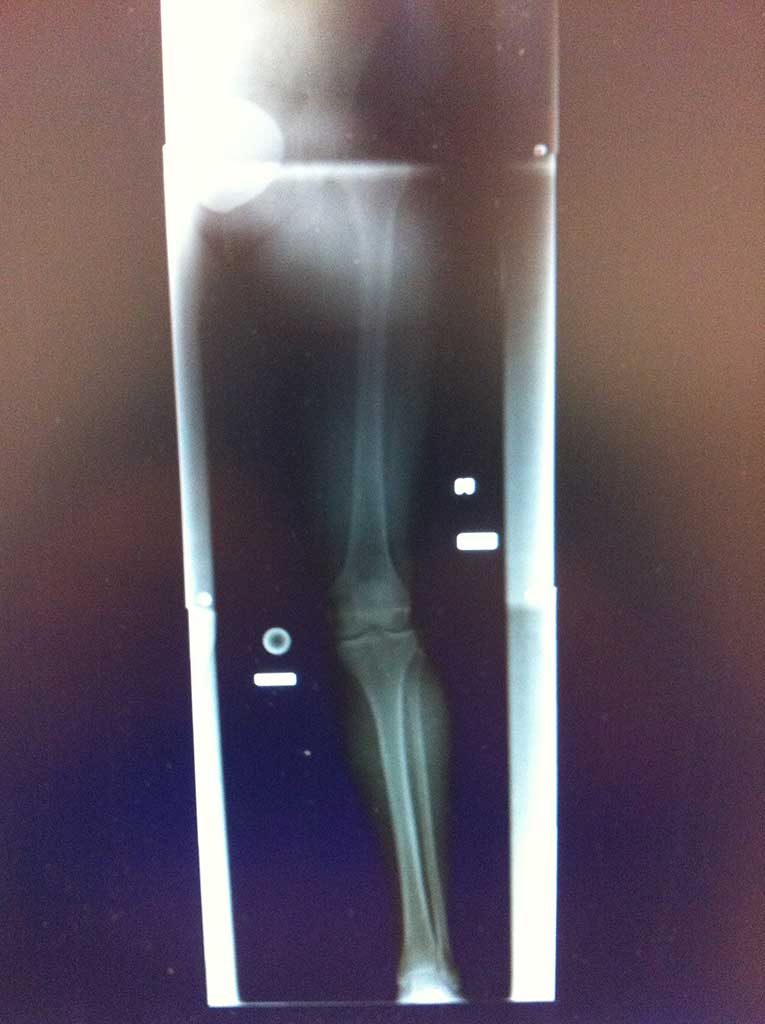

Das Kniegelenk besteht aus 2 langen Rohrknochen (Oberschenkelknochen und Schienbein / Femur und Tibia) und einem Sesambein (Kniescheibe / Patella). Die knöchernen Gelenkflächen sind komplett mit einem einzigartigen Gewebe und zwar dem Hyalingelenkknorpel überzogen. Dieses Gewebe weist extrem geringes Heilungspotenzial auf, da es gefäßlos ist.

Nach präziser arthroskopischer Anlage von zwei Bohrkanälen jeweils ein im Oberschenkelknochen und Schienbeinkopf, wird das VKB Transplantat aus einer oder zwei körpereigenen Sehnen ( Semitendinosus, Gracilis ) ins Kniegelenk eingezogen und in den Kanälen befestigt.